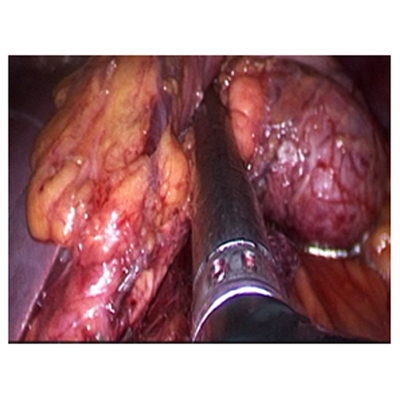

LAPAROSCOPIC SURGERY FOR PANCREATIC TUMOUR

LAPAROSCOPIC SURGERY FOR RECTAL CANCER

LAPAROSCOPIC WHIPPLES PROCEDURE